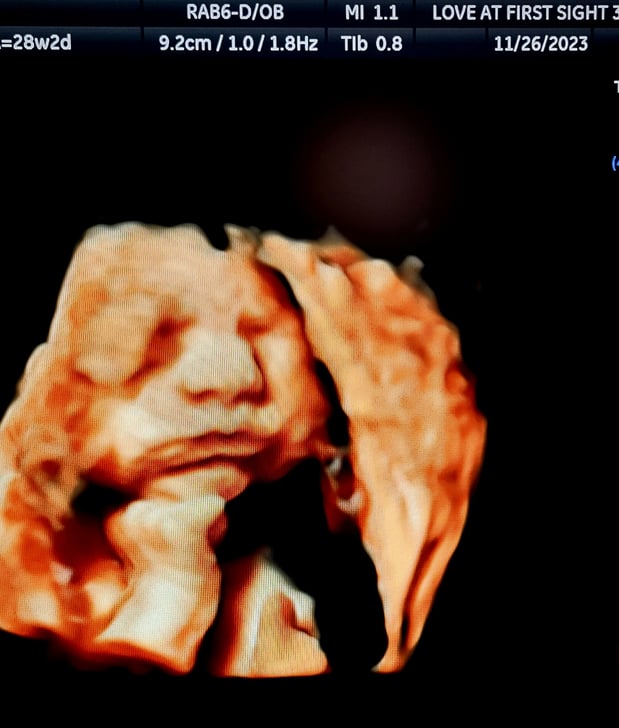

Tasha Crump, is registered by the American Registry of Diagnostic Medical Sonographers (ARDMS) and have over 18 years experience in medical diagnostic sonography specializing in Maternal Fetal Medicine. She is a highly proficient in the art of 3D 4D ultrasound. Tasha has practiced and trained in NYC's top ranked hospitals including Columbia Presbyterian. At Love at First Sight Imaging Studio you'll be in a very comfortable and calming atmosphere for you and your family to bond with your baby. We have state of the art equipment with HD Live to image unbelievably realistic views of your baby. You will fall in Love at First Sight.